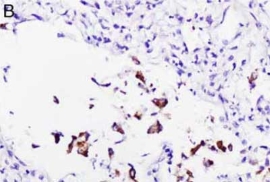

检测肺部组织中的SARS-CoV-2

|

检测SARS-CoV-2 RNA。A和B分别为使用竞品和Enzo探针在COVID-19肺炎样品中进行SARS-CoV-2 RNA原位杂交。竞品探针还会标记巨噬细胞(图A中圆圈部分)。

Nuovo GJ et Al. Appl Immunohistochem Mol Morphol. 2022 Feb 1;30(2):83-90.